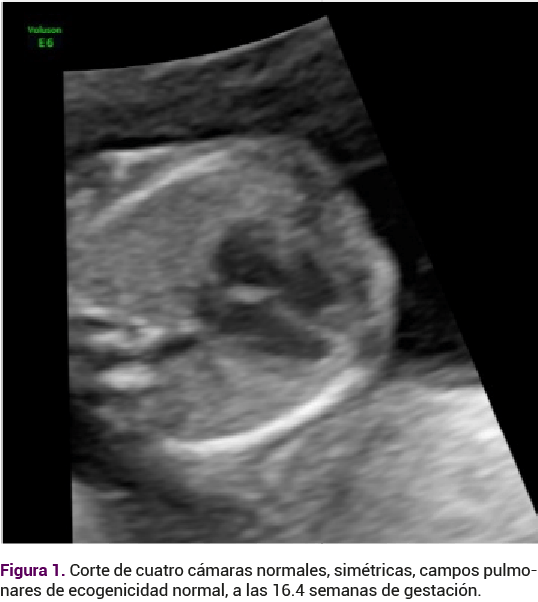

A su ingreso a la clínica se le practicó un ultrasonido obstétrico institucional por parte de un especialista en medicina materno fetal. Inicialmente se documentó la existencia de un feto con actividad cardiaca adecuada, peso estimado de 212 gramos, crecimiento adecuado, con situs solitus corte de cuatro cámaras normales, simétricas, campos pulmonares de ecogenicidad normal (Figura 1). En la región occipital derecha de la cabeza del feto se observó una imagen quística anecoica supratentorial, localizada en el espacio subaracnoideo que desplazaba al parénquima hacia la región anterior y a la línea media hacia el lado contralateral, sin evidencia de flujo al Doppler color, que midió 16 x 11 mm (Figura 2). En ese momento la imagen era sugerente de un hematoma subaracnoideo occipital derecho. Los tálamos, pedúnculos cerebrales, tabique doble, vertical y triangular se localizaron en la línea media. La fosa posterior era de aspecto normal. El sistema ventricular no estaba dilatado. La calota fetal se observó íntegra. El resto del estudio morfológico fetal se advirtió en parámetros de normalidad.

<strong>Figura 1</strong>

Figura 1.